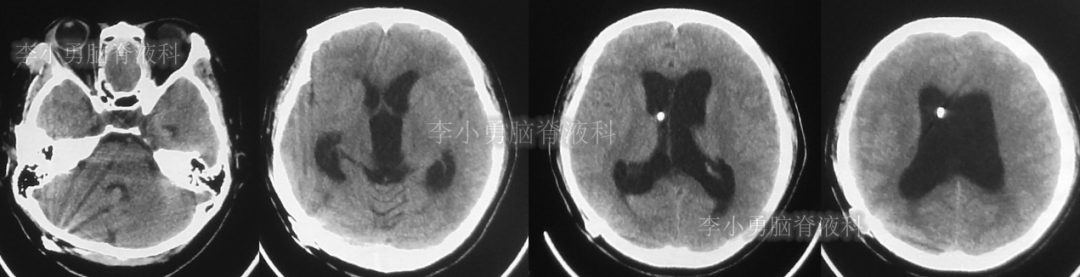

此后1个多月(2019年11月4日到2019年12月16日),患者意识一直无改善,一直呈模糊状态,多次复查头颅CT(图-12至图-20)见脑室大小反复变化不定,医生根据CT结果等反复多次调节分流泵压力(具体过程家属回忆不起)。但患者病情无好转却逐渐加重,逐渐不能咀嚼、吞咽及进食,卧床不起。

图-12:2019年11月8日头颅CT

图-13:2019年11月16日头颅CT

图-14:2019年11月19日头颅CT

图-15:2019年12月3日头颅CT

图-16:2019年12月10日头颅CT

图-17:2019年12月12日头颅CT

图-18:2019年12月13日头颅CT

图-19:2019年12月14日头颅CT

图-20:2019年12月16日头颅CT